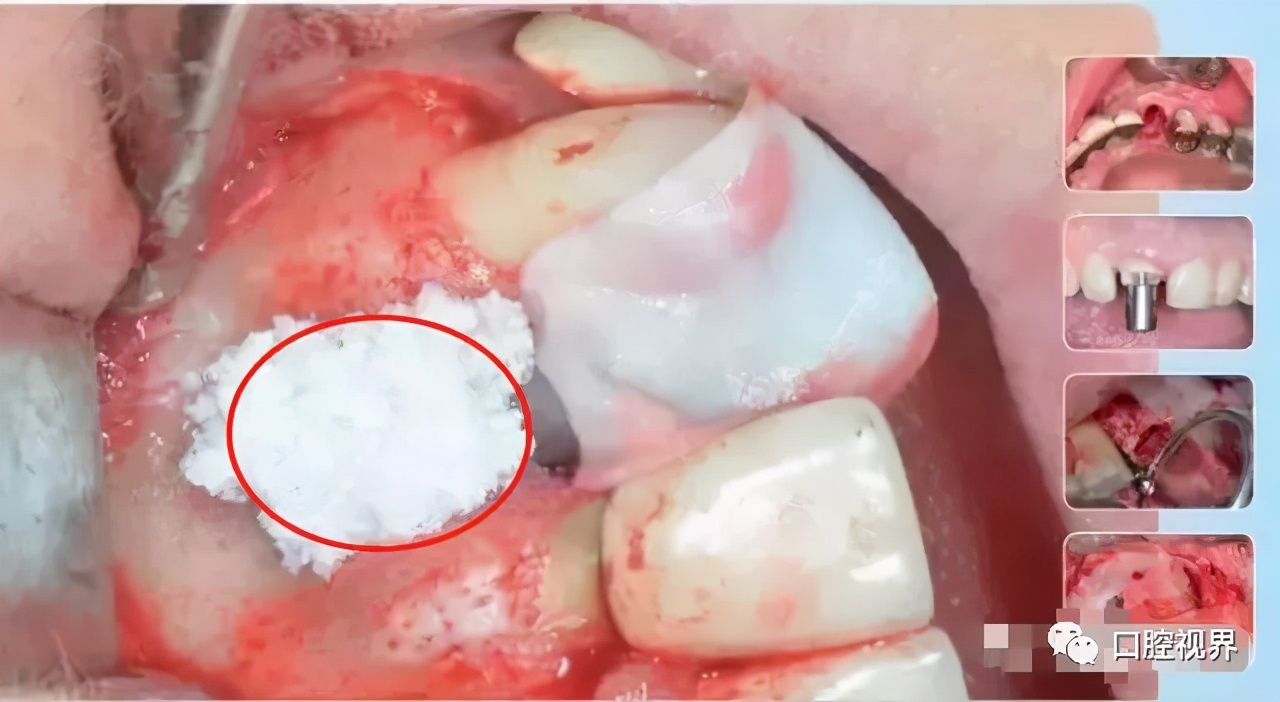

位点保存指的是拔牙的同时或随后,采取的一种减少牙槽骨吸收,促进牙槽内新骨形成的一系列治疗方法。

就是将口腔专用的骨粉骨粒植入牙创口,在面上再覆盖一层可吸收膜,从而达到修复牙槽骨的作用。

临床研究表明,拔牙术后牙槽骨可能会因此减少,有些骨板过薄的甚至会被完全吸收,而位点保存正是为此而存在的。

这足以以假乱真的修复方式,不仅是为了保存牙槽骨,更是为后期种植牙做好前提条件。

这种情况下是可以考虑进行位点保存手术的。如图——